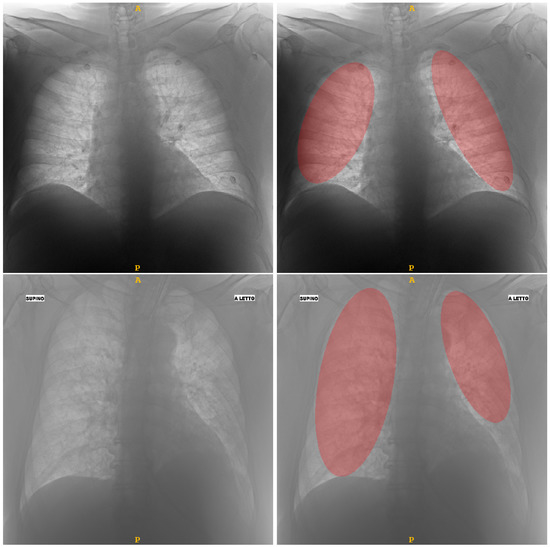

To extract the radiomic features, the regions of interest (ROIs) containing the lungs have to be identified. To achieve this, a MATLAB®-coded custom tool was implemented to delineate the lung ROIs: in particular, a semi-automatic delineation modality for the identifying of the maximum elliptical ROI contained within the lung was implemented. This choice was motivated by the need to focus the attention on the central region of the lung, excluding peripheral zones. In Figure 1 two segmentation examples. Due to the excessive heterogeneity of the CXR dataset, automatic lung segmentation approaches did not provide satisfactory results. For this reason, it was decided to implement a tool that can easily support clinicians during the image annotation procedure. Specifically, the implemented semi-automatic algorithm allows the automatic identification of the bounding-box containing the lung and determining the maximum elliptical ROI contained within it. The clinician can decide whether to accept it, if the result is satisfactory, or to modify it to find a more suitable fitting between the elliptic ROI and the lung area by changing orientation and size of the ellipse. Because this is a supervised semi-automatic approach (each segmentation is directly validated), and considering the experience of the clinicians who supported this study, no evaluation step was performed. We decided to implement an ad hoc computer-assisted tool that can simply and intuitively guide clinicians through the steps of lung segmentation, from CXR image selection to segmentation mask storage.

Figure 1.

Two examples of segmentation obtained by means of the semi-automatic tool able to assist clinician to detect the elliptical ROIs (highlighted in red) within lungs: in the upper row a MILD sample; in the lower row a SEVERE sample.